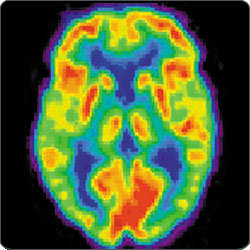

Ich möchte zunächst einmal auf das bekannt gewordene Libet-Experiment zu sprechen kommen, das vor etwa drei, vier Jahren neu aufgelegt wurde: teils sehr erfahrene Neurowissenschaftler haben dabei mittels funktioneller Magnetresonanztomographie (FMRT) versucht empirisch nachzuweisen, dass bewusste Handlungsentscheidungen des Menschen schon bis zu zehn Sekunden vorher von bestimmten Hirnregionen vermutlich unbewusst beeinflusst werden.

Foto: „Positron emission tomography image of a human brain“ von BlatantNews.com (unter einer Creative Commons Lizenz).